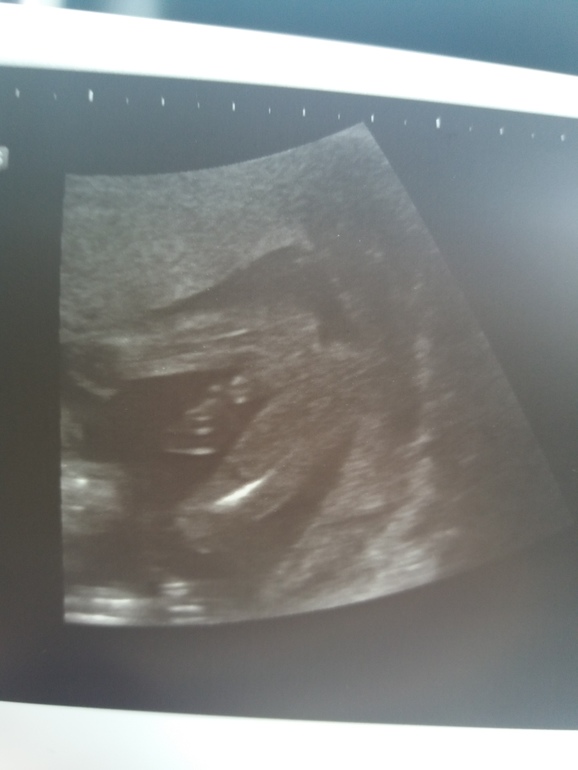

Ой я тоже из тех кто сначала хотела девочку, но на 12ой неделе сказали 98% процентов мальчик, и на 22ой неделе подтвердили 100%, хвостик никуда не делся

На 13 неделях предположили мальчка, причем на 13,2 я переделывала УЗИ и на 3Д сказали, точно - мальчик! В 16 недель сказали девочка, потом такие ой не, подождите, вот, мальчик))) скоро 2-й скрининг, надеюсь, там ничего не рассосалось))))